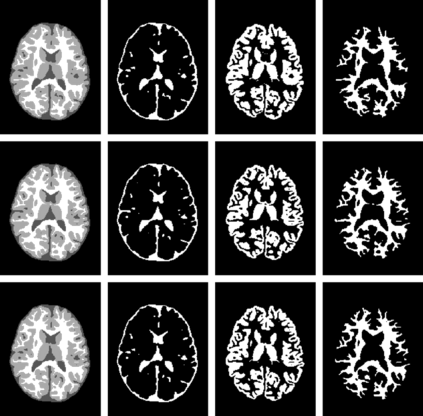

An important step in early brain development study is to perform automatic segmentation of infant brain magnetic resonance (MR) images into cerebrospinal fluid (CSF), gray matter (GM) and white matter (WM) regions. This task is especially challenging in the isointense stage (approximately 6-8 months of age) when GM and WM exhibit similar levels of intensities in MR images. Deep learning has shown its great promise in various image segmentation tasks. However, existing models do not have an efficient and effective way to aggregate global information. They also suffer from information loss during up-sampling operations. In this work, we address these problems by proposing a global aggregation block, which can be flexibly used for global information fusion. We build a novel model based on 3D U-Net to make fast and accurate voxel-wise dense prediction. We perform thorough experiments, and results indicate that our model outperforms previous best models significantly on 3D multimodality isointense infant brain MR image segmentation.